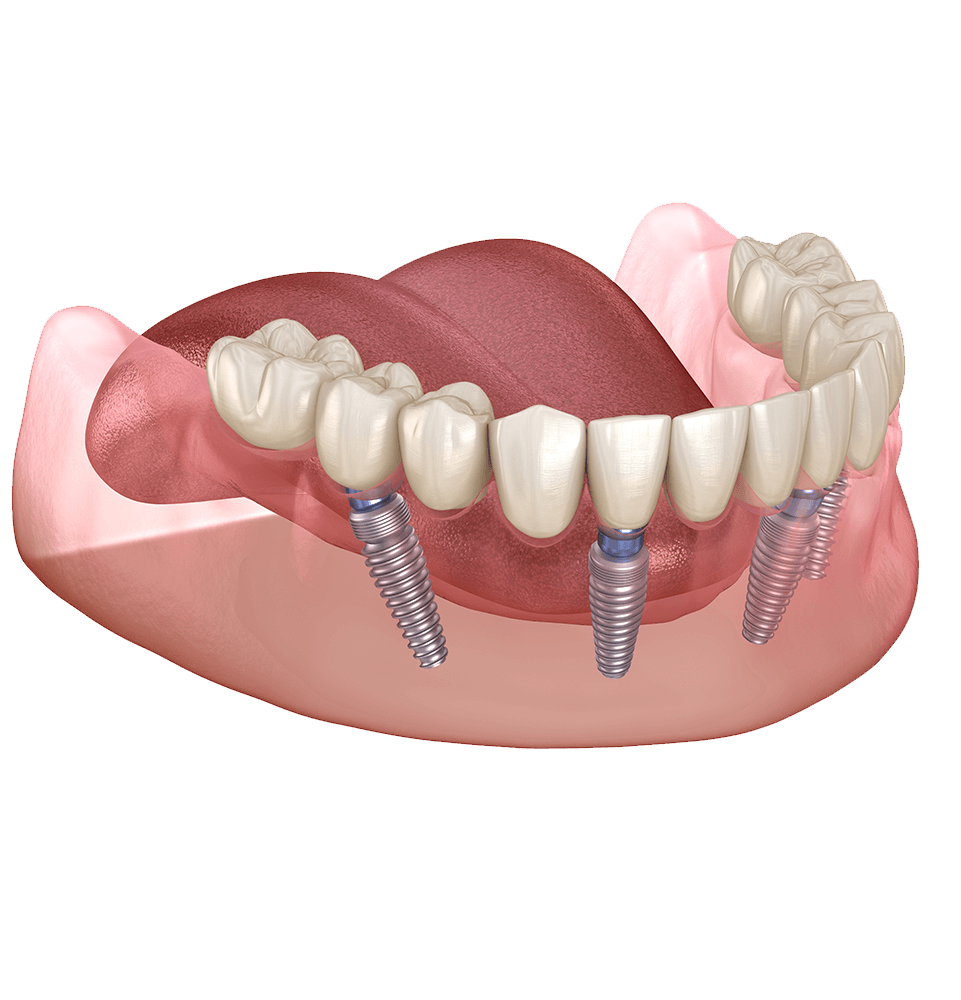

Dental implants consist of metal posts that act as substitutes for tooth roots and artificial teeth that closely mimic and perform like natural teeth. Each element, including the implant fixture, abutment, and dental prosthetic, plays a crucial role in guaranteeing the durability and endurance of the dental implant.

Full arch implant therapy are a streamlined implant solution that replaces missing upper, lower, or both arches using a minimum of four dental implants per arch. They simulate the look and feel of natural teeth and stay fixed in place because they provide a secure and stable foundation. In contrast to traditional dentures, full mouth dental implants in Mesa, AZ, eliminate movement, gum irritation, food limitations, and a sunken-in look caused by ongoing bone resorption. And if our implant dentists determine it is clinically appropriate, you can leave our practice the same day as surgery with a temporary set of new teeth!